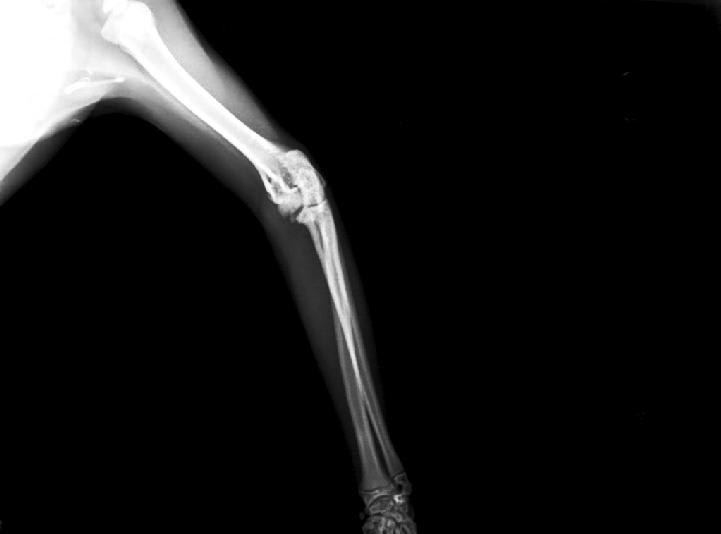

My kitten is one year old, she has calicivirus and has been diagnosed with osteoarthritis. These are hers x-rays. My vet doesn't want to operate. I don't know what to do. Sorry for my grammar mistakes, I am not native english.

Hello, sorry to hear about Kairi. It sounds like besides her calicivirus, she is having some difficult time walking? If so, it is believed that this is secondary to osteoarthritis. Young cats with osteoarthritis can often have more than one joint affected and is often something that is management medically. Finding the underlying cause for this osteoarthritis such as infection, an inflammatory response, auto-immune disease, or an old injury must be determined. Surgery may not be able to treat the osteoarthritis but rather help her walk easier. Surgical intervention is often pursued as a salvage procedure and not before diagnosing the source of the osteoarthritis and its effect. I would recommend asking your veterinarian to refer Kairi to an orthopedic surgeon so that they may evaluate her and determine if one or more joints are affected and if surgery or medical management is best for her. Hope this helps and best of luck.